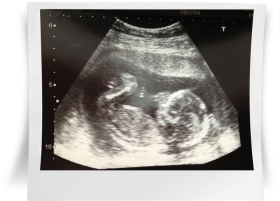

Вы на 4 месяце беременности, развитие плода продолжается, впереди осталось еще пять месяцев до появления на свет Вашего малыша1. На снимках УЗИ видны все части тела Вашего крохи, а также внутренние органы.

Кстати, шевеления плода в 15 недель беременности хорошо видны на УЗИ, они носят еще непроизвольный, а рефлекторный характер, и при проведении УЗИ Вы их легко различите.